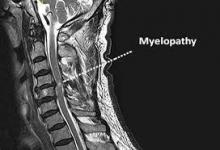

Η αυχενική δισκοκήλη είναι η προβολή του μεσοσπονδυλίου δίσκου στον νωτιαίο σωλήνα, λόγω φθοράς του ινώδους δακτυλίου που τον περιβάλλει...